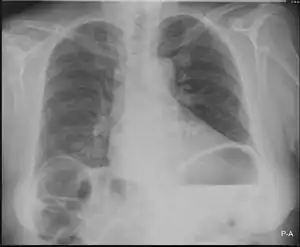

Chilaiditi syndrome is a rare condition when pain occurs due to transposition of a loop of large intestine (usually transverse colon) in between the diaphragm and the liver, visible on plain abdominal X-ray or chest X-ray.[1]

| Chest X-ray showing obvious Chilaiditi's sign, or presence of gas in the right colic angle between the liver and right hemidiaphragm. | |

Normally this causes no symptoms, and this is called Chilaiditi's sign. The sign can be permanently present, or sporadically. This anatomical variant is sometimes mistaken for the more serious condition of having air under the diaphragm (pneumoperitoneum) which is usually an indication of bowel perforation, possibly leading to surgical interventions.